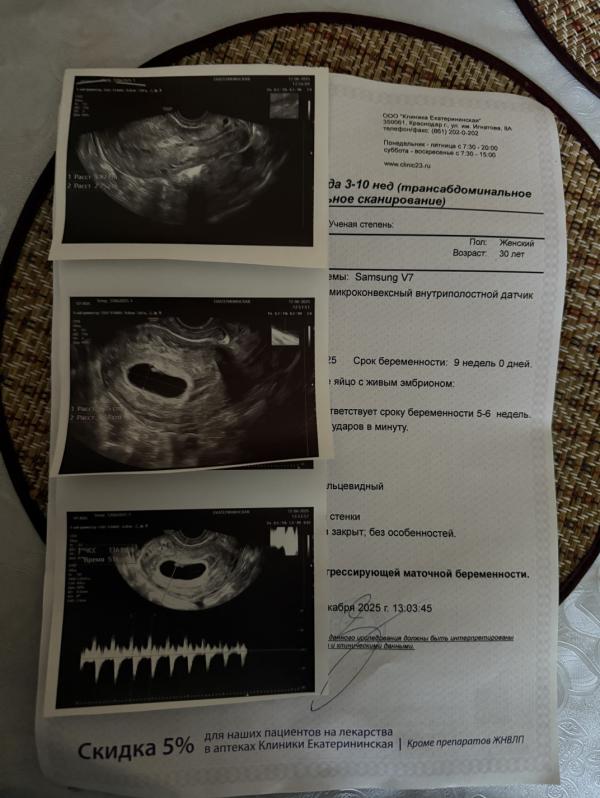

Беременность с тонусом и кровотечением: история с хорошим концом

Мы выросли , все хорошо не смотря на кровотечение из-за тонуса ❤️ сердцебиение появилось 😍